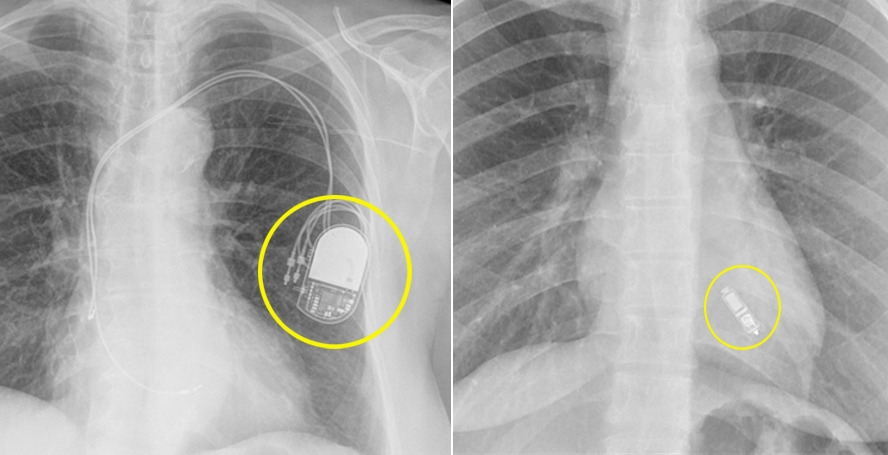

심박동기 비교.jpg [사진] (좌)기존 심장박동기, (우)전극선 없는 무선 심박동기 전극선 없는 무선 심장박동기는 2.6cm 정도의 캡슐 영양제 크기다. 기존 심박동기 부피의 10분의 1정도다. 절개

무전극선 심박동기는 기존 심박동기에 비해 기기 크기가 10분의 1 수준에 불과한 2.6cm로, 전극선이 없는 캡슐형 기기입니다. 가슴을 절개하지 않고 허벅지 부위의 대퇴정맥을 통해 심장 내에 삽입할 수 있어 시술 부담이 적고 회복 속도가 빠르며, 합병증 위험 또한 현저히 낮습니다.